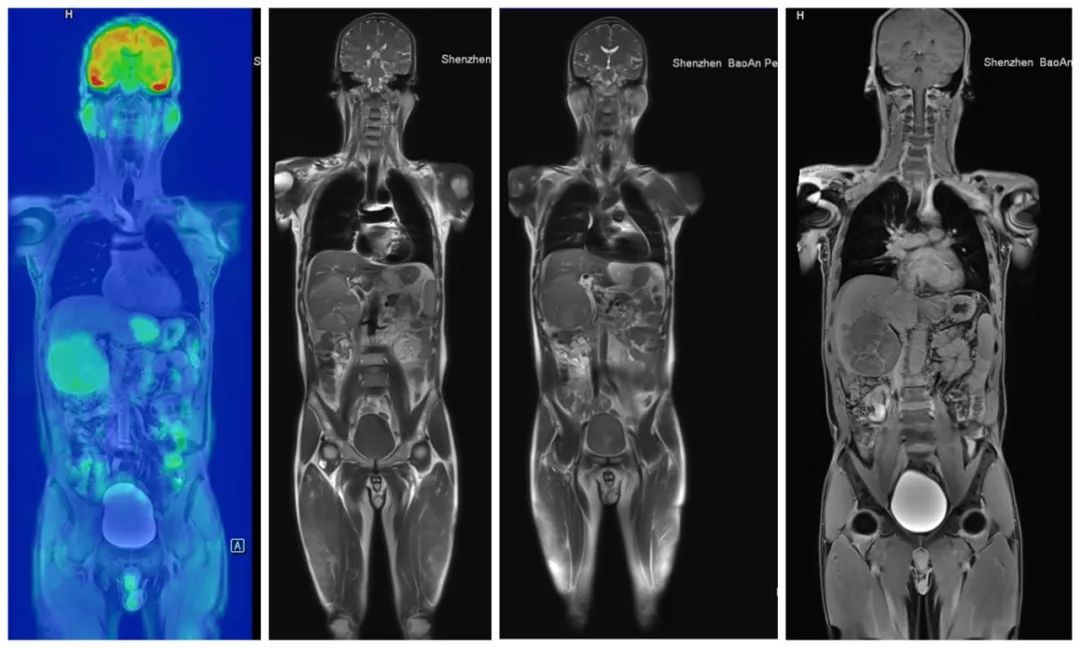

这台机器配备有目前国际上 MR 检查最全最新的功能序列,包括目前仅在国外大学科研中才用到的功能成像序列,它们可以提供组织器官和病变部位更多的分子和代谢功能信息,帮助临床诊断更准确。

也就是说,除了特殊情况,患者不需要注射造影剂,医生也能对他们的血管,淋巴结或肿块进行准确判断。

另外,新机器还可以实现一次屏气多动脉期快速成像,精确显示病变动态变化,由此发现之前不可见的病灶。

它拍出来的图像都是啥样?随意感受下......

全身类PET